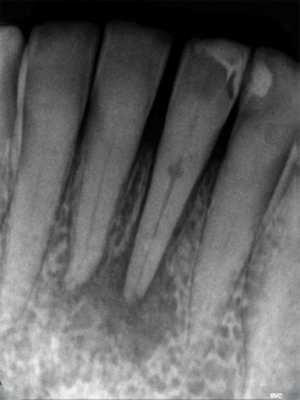

Часто резорбцию выявляют случайно при рентгенологическом исследовании по другому поводу [23] . На рентгенограмме внутренняя и внешняя резорбция будут выглядеть по-разному.

Рентгенологические признаки наружной и внутренней резорбции корня зуба

Воспалительная и заместительная резорбция рентгенологически очень похожи. Но при заместительной резорбции из-за образования кости на снимке не видно просветления в области периодонтальной щели.

Фото 1. Рентгенограмма, демонстрирующая пример внутренней резорбции корня.

Фото 2. Рентгенограмма, демонстрирующая пример внешней воспалительной резорбции корня.

Фото 3. Рентгенограмма, демонстрирующая пример резорбции по причине давления.